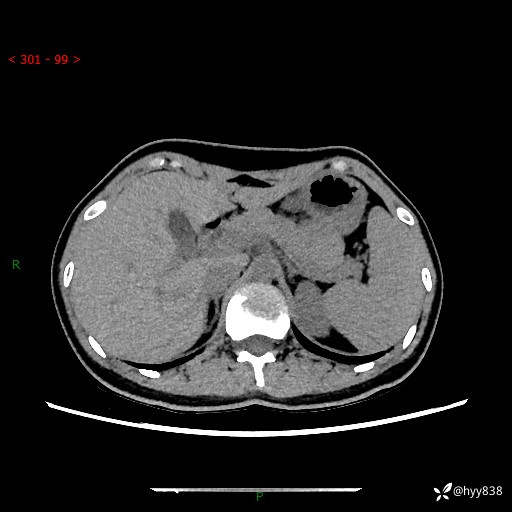

性别:女

年龄:23岁

简要病史:外院发现肝结节,来我院进一步增强确诊

上腹部CT平扫+增强